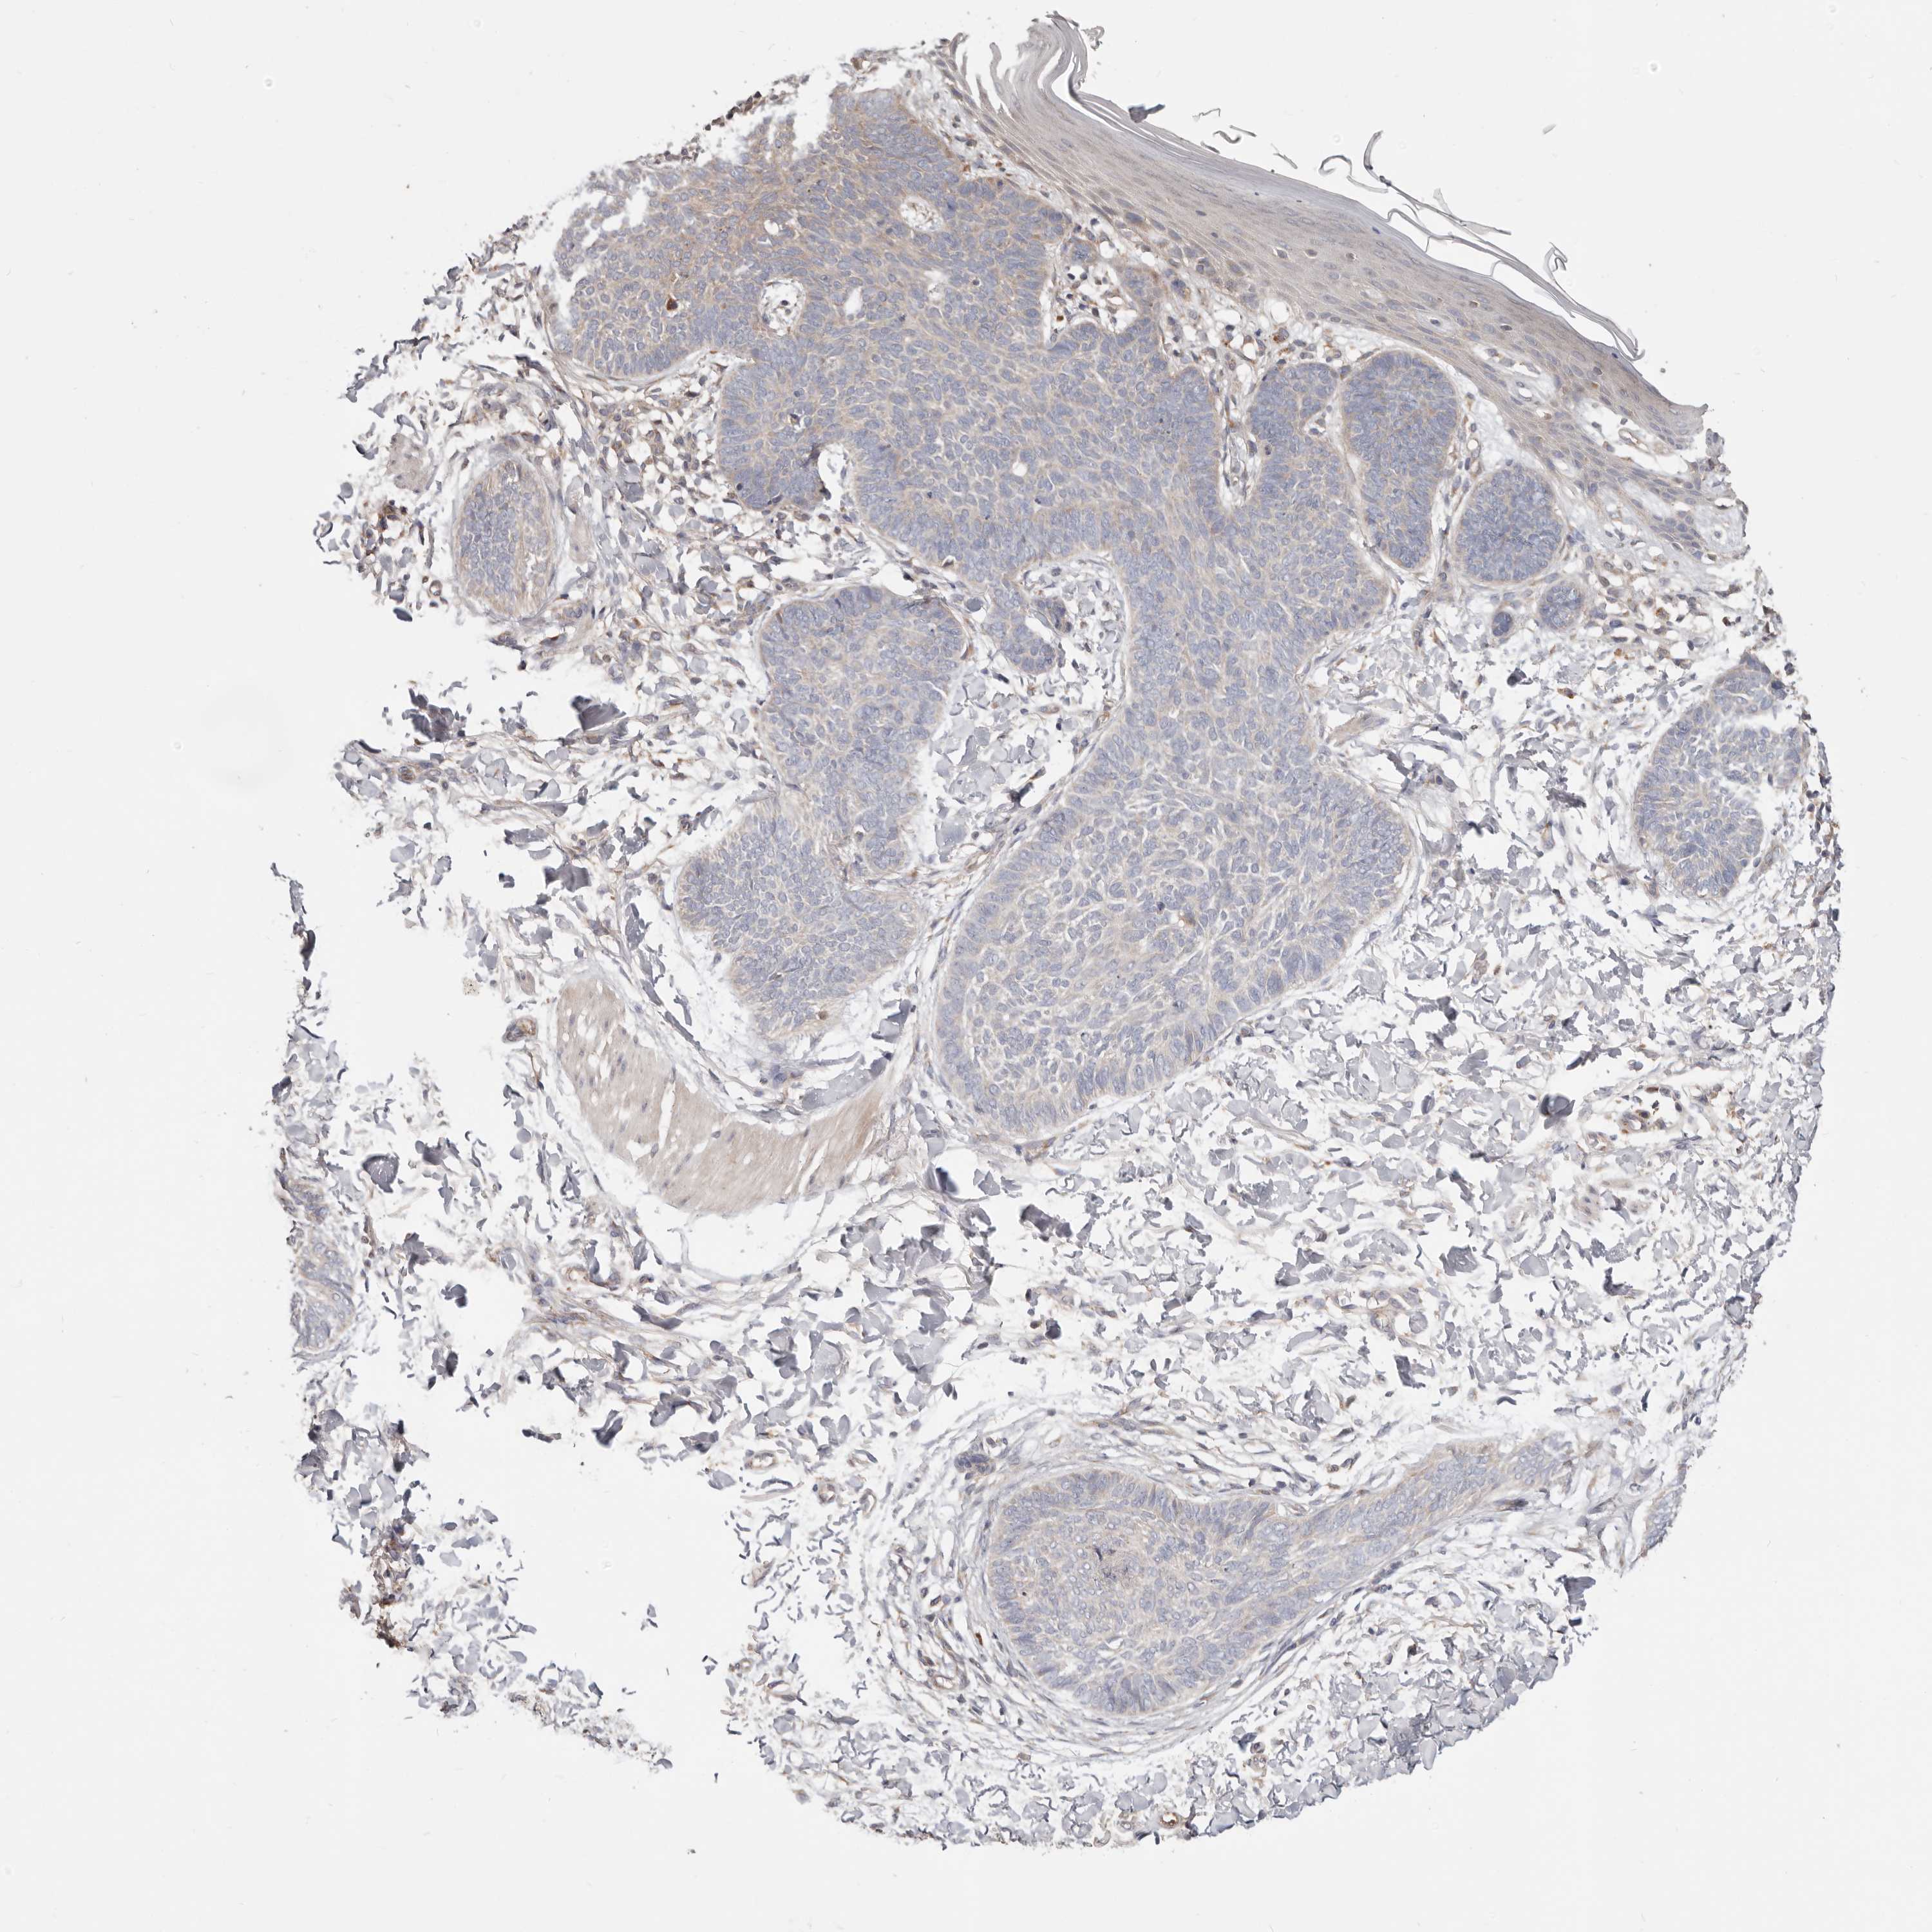

Basal cell and squamous cell cancer

SKIN CANCER - Protein expressioni

A mouse-over function shows sample information and annotation data. Click on an image to view it in a full screen mode. Samples can be filtered based on level of antibody staining by selecting one or several of the following categories: high, medium, low and not detected. The assay and annotation is described here.

Antibody stainingi

Antibody staining in the annotated cell types in the current human tissue is reported as not detected, low, medium, or high, based on conventional immunohistochemistry profiling in selected tissues. This score is based on the combination of the staining intensity and fraction of stained cells.

Each image is clickable and will lead to virtual microscopy that enables deeper exploration of all samples and also displays staining intensity scores, fraction scores and subcellular localization as well as patient and tissue information for each sample.

Antibody HPA029925

Antibody CAB004490

Basal cell carcinoma

Squamous cell carcinoma, NOS